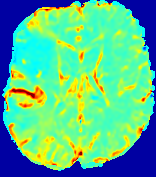

LesionRefer to captionRefer to captionRefer to captionRefer to captionRefer to captionRefer to caption𝐕rgbsubscript𝐕𝑟𝑔𝑏{\bf{V}}_{rgb}Refer to captionRefer to captionRefer to captionRefer to captionRefer to captionRefer to caption𝐕2subscriptnorm𝐕2{\|\bf{V}}\|_{2}Refer to captionRefer to captionRefer to captionRefer to captionRefer to captionRefer to captionRefer to caption3.53.53.52.82.82.82.12.12.11.41.41.40.70.70.70.00.00.0(mm/s)𝑚𝑚𝑠(mm/s)D𝐷DRefer to captionRefer to captionRefer to captionRefer to captionRefer to captionRefer to captionRefer to caption0.0200.0200.0200.0160.0160.0160.0120.0120.0120.0080.0080.0080.0040.0040.0040.0000.0000.000(mm2/s)𝑚superscript𝑚2𝑠(mm^{2}/s)Slice #1Slice #2Slice #3Slice #4Slice #5Slice #6

Figure 3: PIANO feature maps for one stroke patient, where the lesion is located in the left hemisphere. Top row: segmented stroke lesion region (white) on different slices, obtained from ISLES 2017. The corresponding slices for the PIANO feature maps are shown in the following rows.

For a better insight into an estimated velocity field 𝐕𝐕{\bf{V}} and diffusion field 𝐃𝐃{\bf{D}}, we compute the following maps: (1) 𝐕rgbsubscript𝐕𝑟𝑔𝑏{\bf{V}}_{rgb}: Color-coded orientation map of 𝐕=(Vx,Vy,Vz)T𝐕superscriptsuperscript𝑉𝑥superscript𝑉𝑦superscript𝑉𝑧𝑇{\bf{V}}=(V^{x},V^{y},V^{z})^{T}, obtained by normalizing 𝐕𝐕{\bf{V}} to unit length and mapping its 3 components to red, green, blue respectively; (2) 𝐕2subscriptnorm𝐕2\|{\bf{V}}\|_{2}: 222 norm of 𝐕𝐕{\bf{V}}; (3) D𝐷D: scalar field in Eq. 5.

Fig. 3 and Fig. 4 show the PIANO feature maps estimated from two ISLES 2017 patients: all are highly consistent with the lesion in both cases. Details of the blood flow trajectories are revealed in 𝐕rgbsubscript𝐕𝑟𝑔𝑏{\bf{V}}_{rgb} by the ridged patterns and the sharp changes of colors in the unaffected (right) hemisphere, while the flat patterns appearing within the lesion provide little directional information about the velocity and indicate low velocity magnitudes. Velocity magnitudes are more directly visualized via 𝐕2subscriptnorm𝐕2\|{\bf{V}}\|_{2}, from which one can easily locate the lesion where 𝐕2subscriptnorm𝐕2\|{\bf{V}}\|_{2} is low. D𝐷D also indicates lower diffusion values in the lesion, though with less contrast potentially due to the fact that it captures the accumulated effect of CA diffusion at the voxel-level.